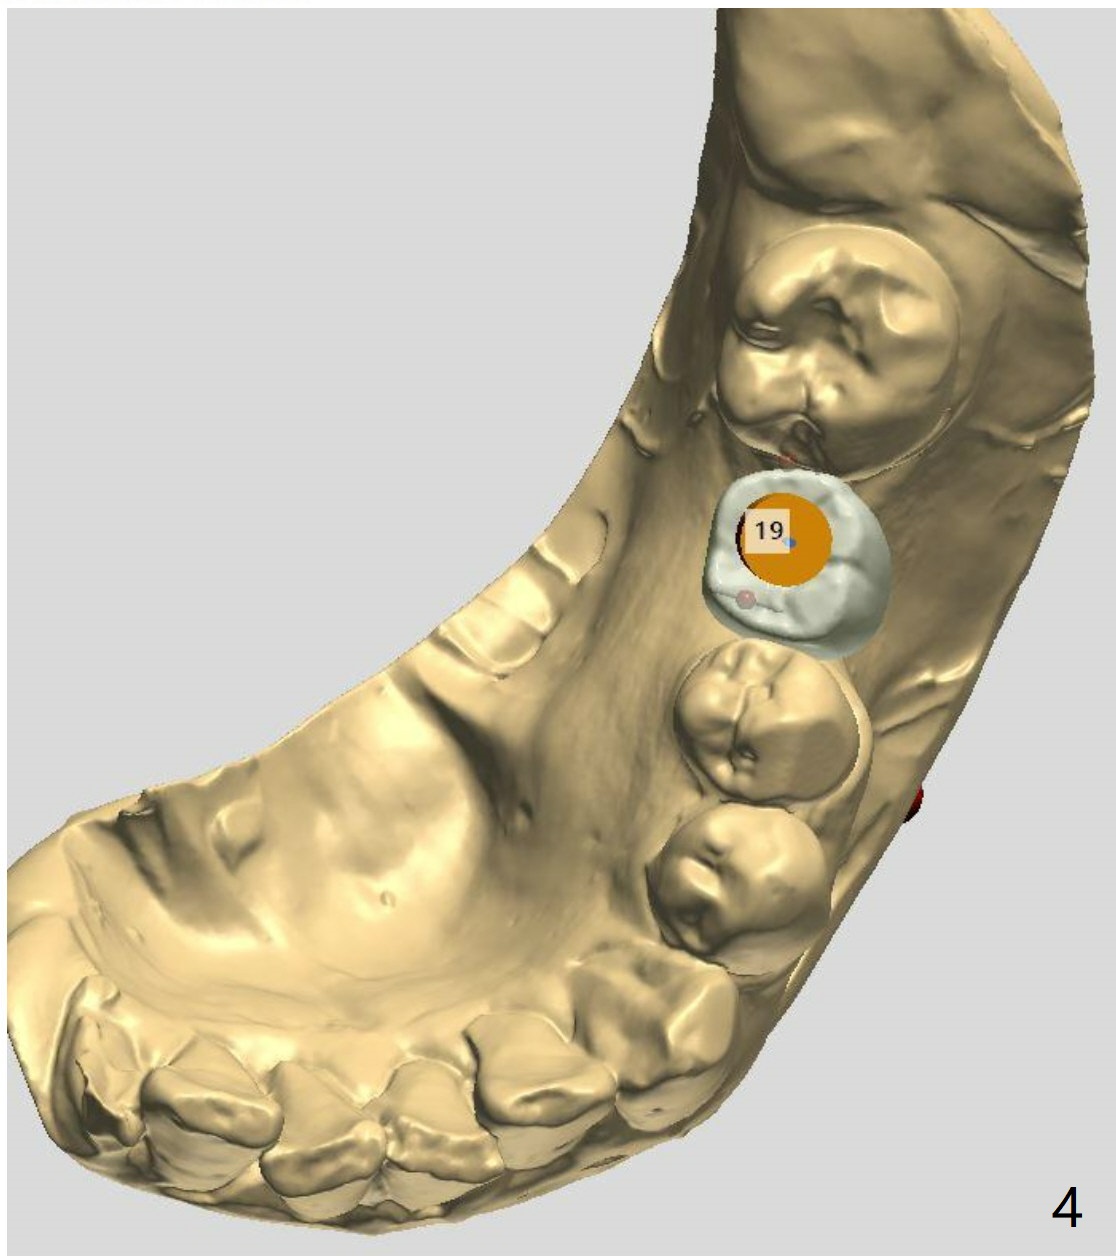

Distal Placement of Narrow Implant for Upright

A 57-year-old woman agrees to orthodontically upright #18 associated with #19 implant placement after #12 implant placement.